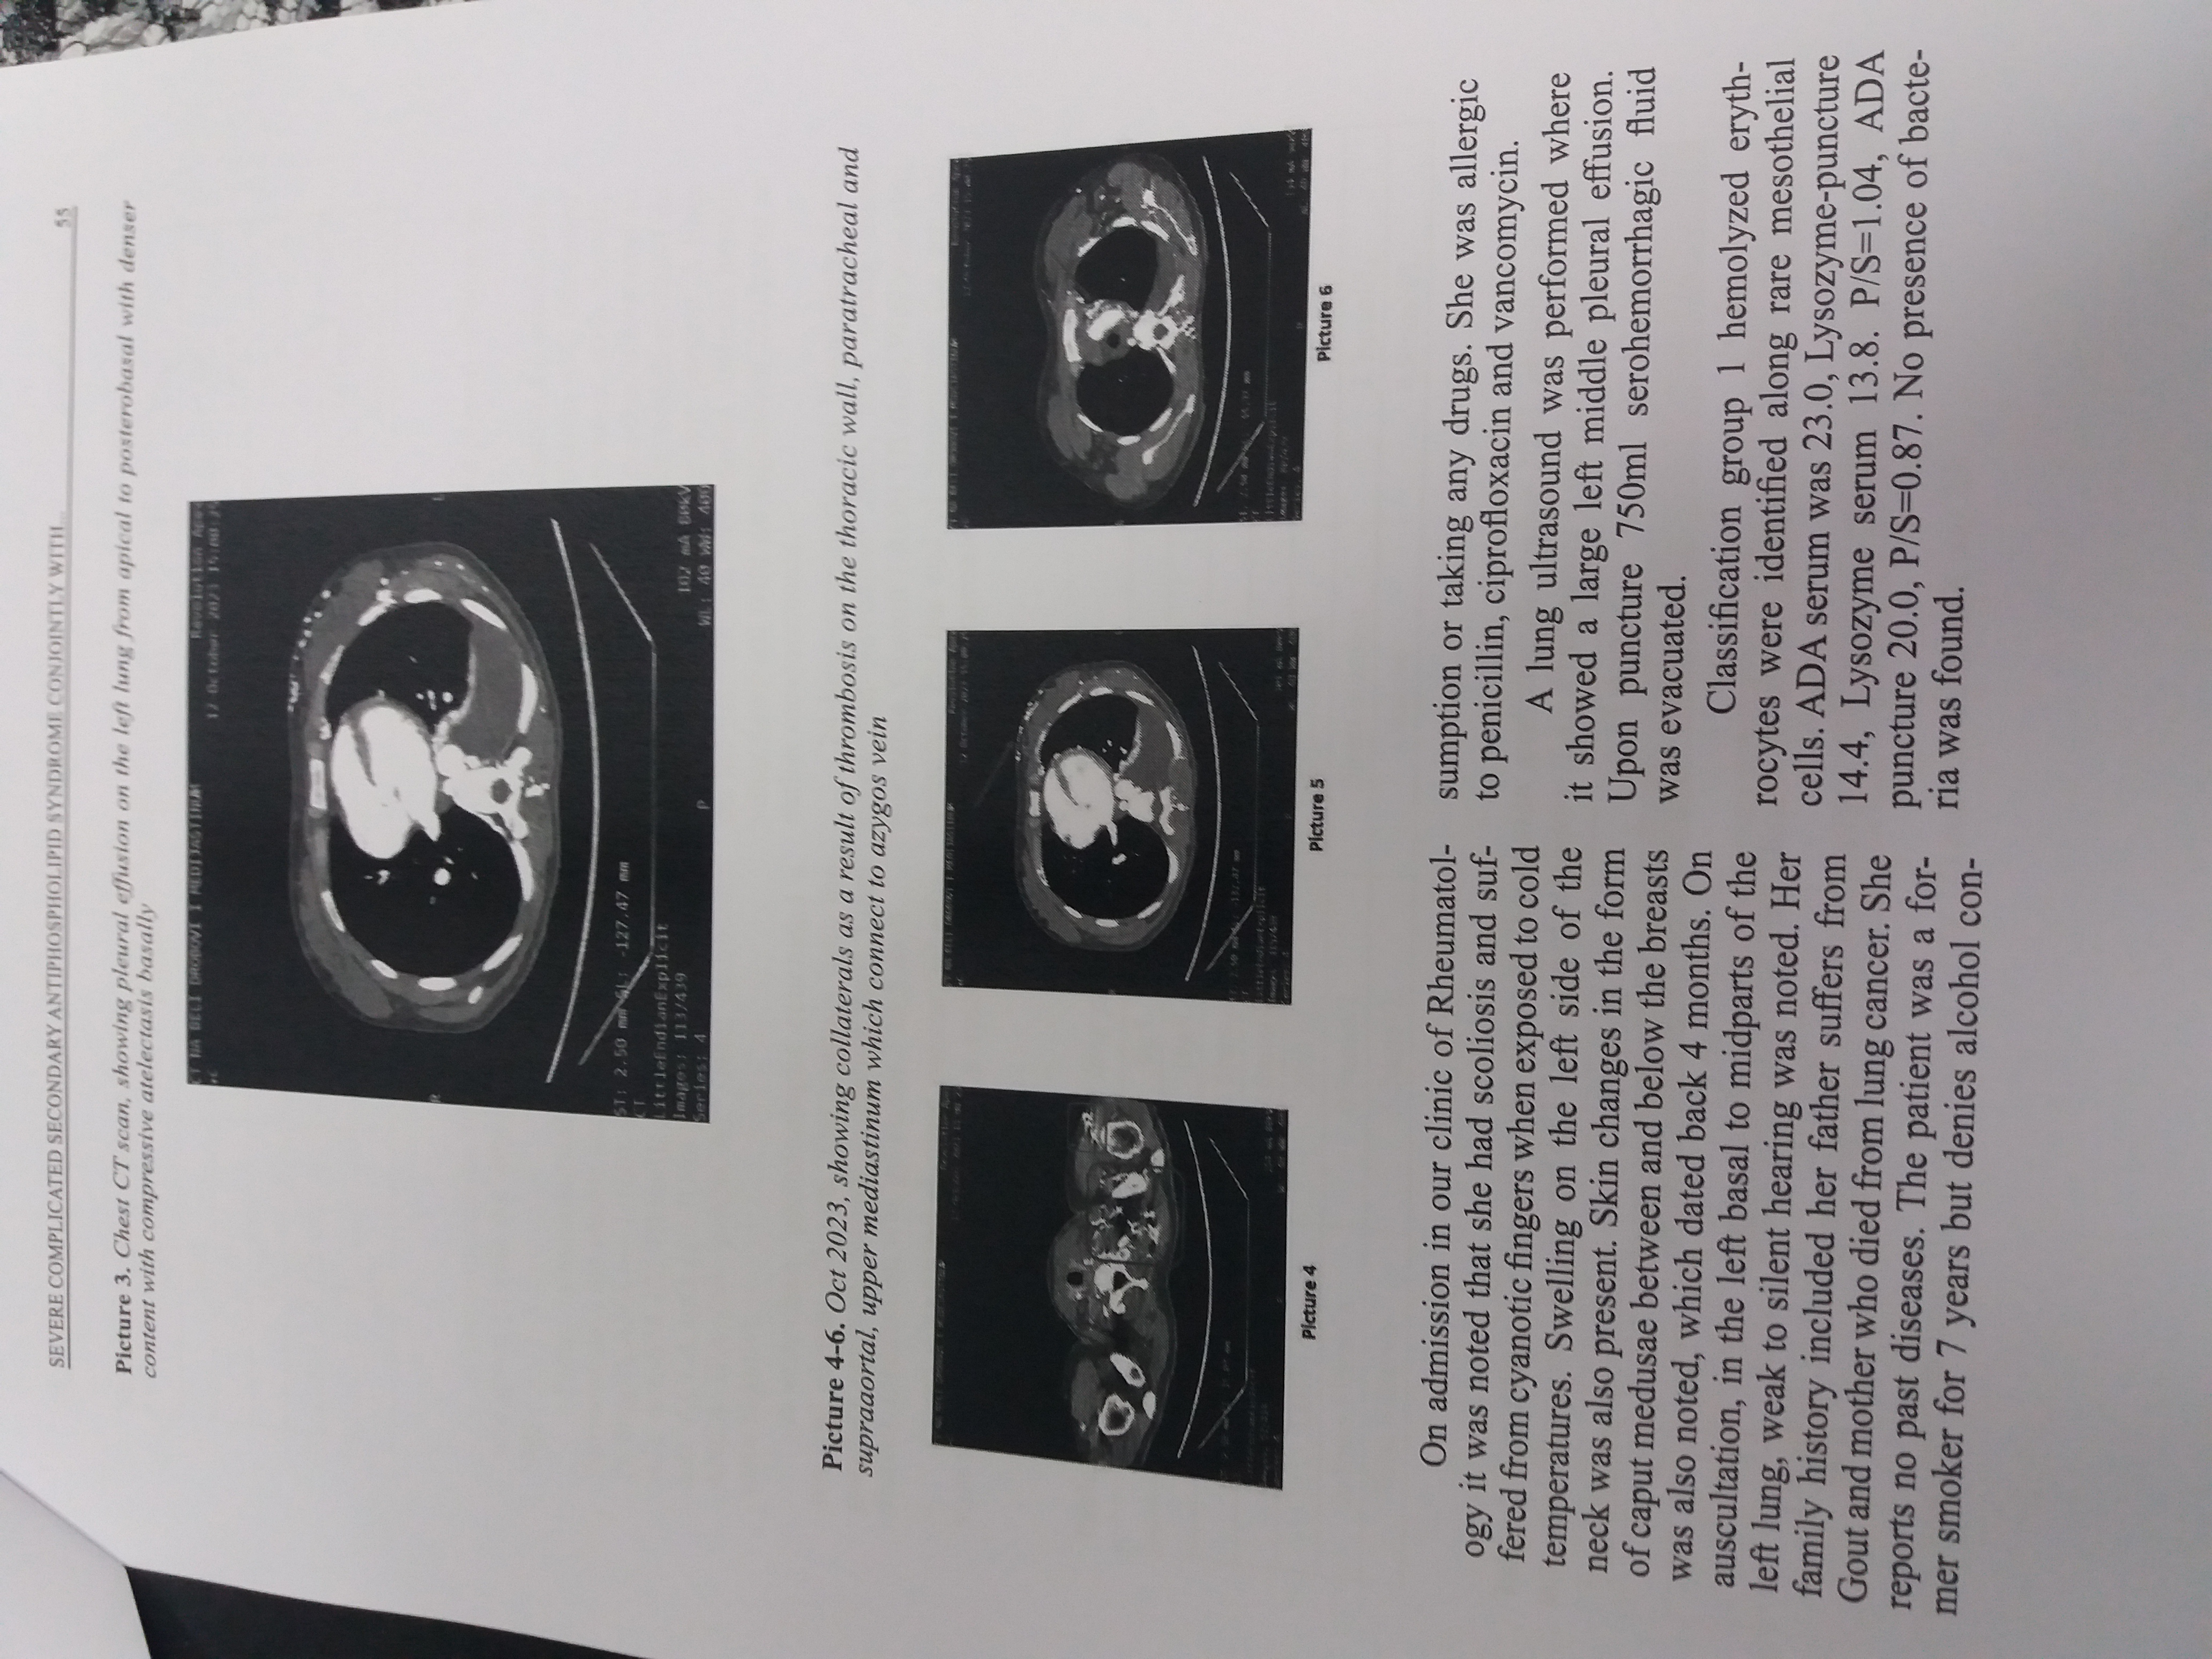

Issue Date: | Jan-2025 | Publisher: | Macedonian Academy of Sciences and Arts/Walter de Gruyter GmbH | Journal: | Prilozi (Makedonska akademija na naukite i umetnostite. Oddelenie za medicinski nauki) | Abstract: | Antiphospholipid syndrome (APS), is an autoimmune systemic disorder known to manifest with thrombosis in almost all vessels throughout the body, can also be accompanied by pregnancy morbidity, and is persistent with the presence of antiphospholipid antibodies, including lupus anticoagulant antibodies, or relatively high titers of anticardiolipin, or anti-β2Glycoprotein I antibodies. APS can occur alone or in association with other diseases, more commonly systemic lupus erythematous. In patients with both underlying diseases episodes of arthritis, skin changes in the form of livedo reticularis, thrombocytopenia and leucopenia were more common. Cardiac manifestations have also been reported. Here we present a complicated case of a young female patient with antiphospholipid syndrome and an underlying systemic lupus erythematosus. | URI: | http://hdl.handle.net/20.500.12188/34378 | ISSN: | 1857-9345 | DOI: | 10.2478/prilozi-2025-0006 |